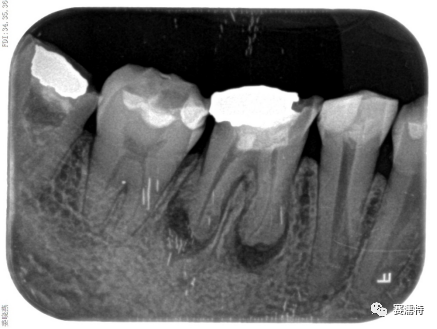

C-Root SP是預混合的、可即刻應用的、可注射的、遇水凝固的硅酸鹽類生物活性陶瓷糊劑材料,主要成分為硅酸鍶、氧化鋯、磷酸鈣、氫氧化鈣,用于根管的密封和永久充填,適合單尖法、側壓法和熱牙膠法。 C-Root SP為世界口腔醫生提供一個“鍶生物陶瓷”的新選擇! >>>